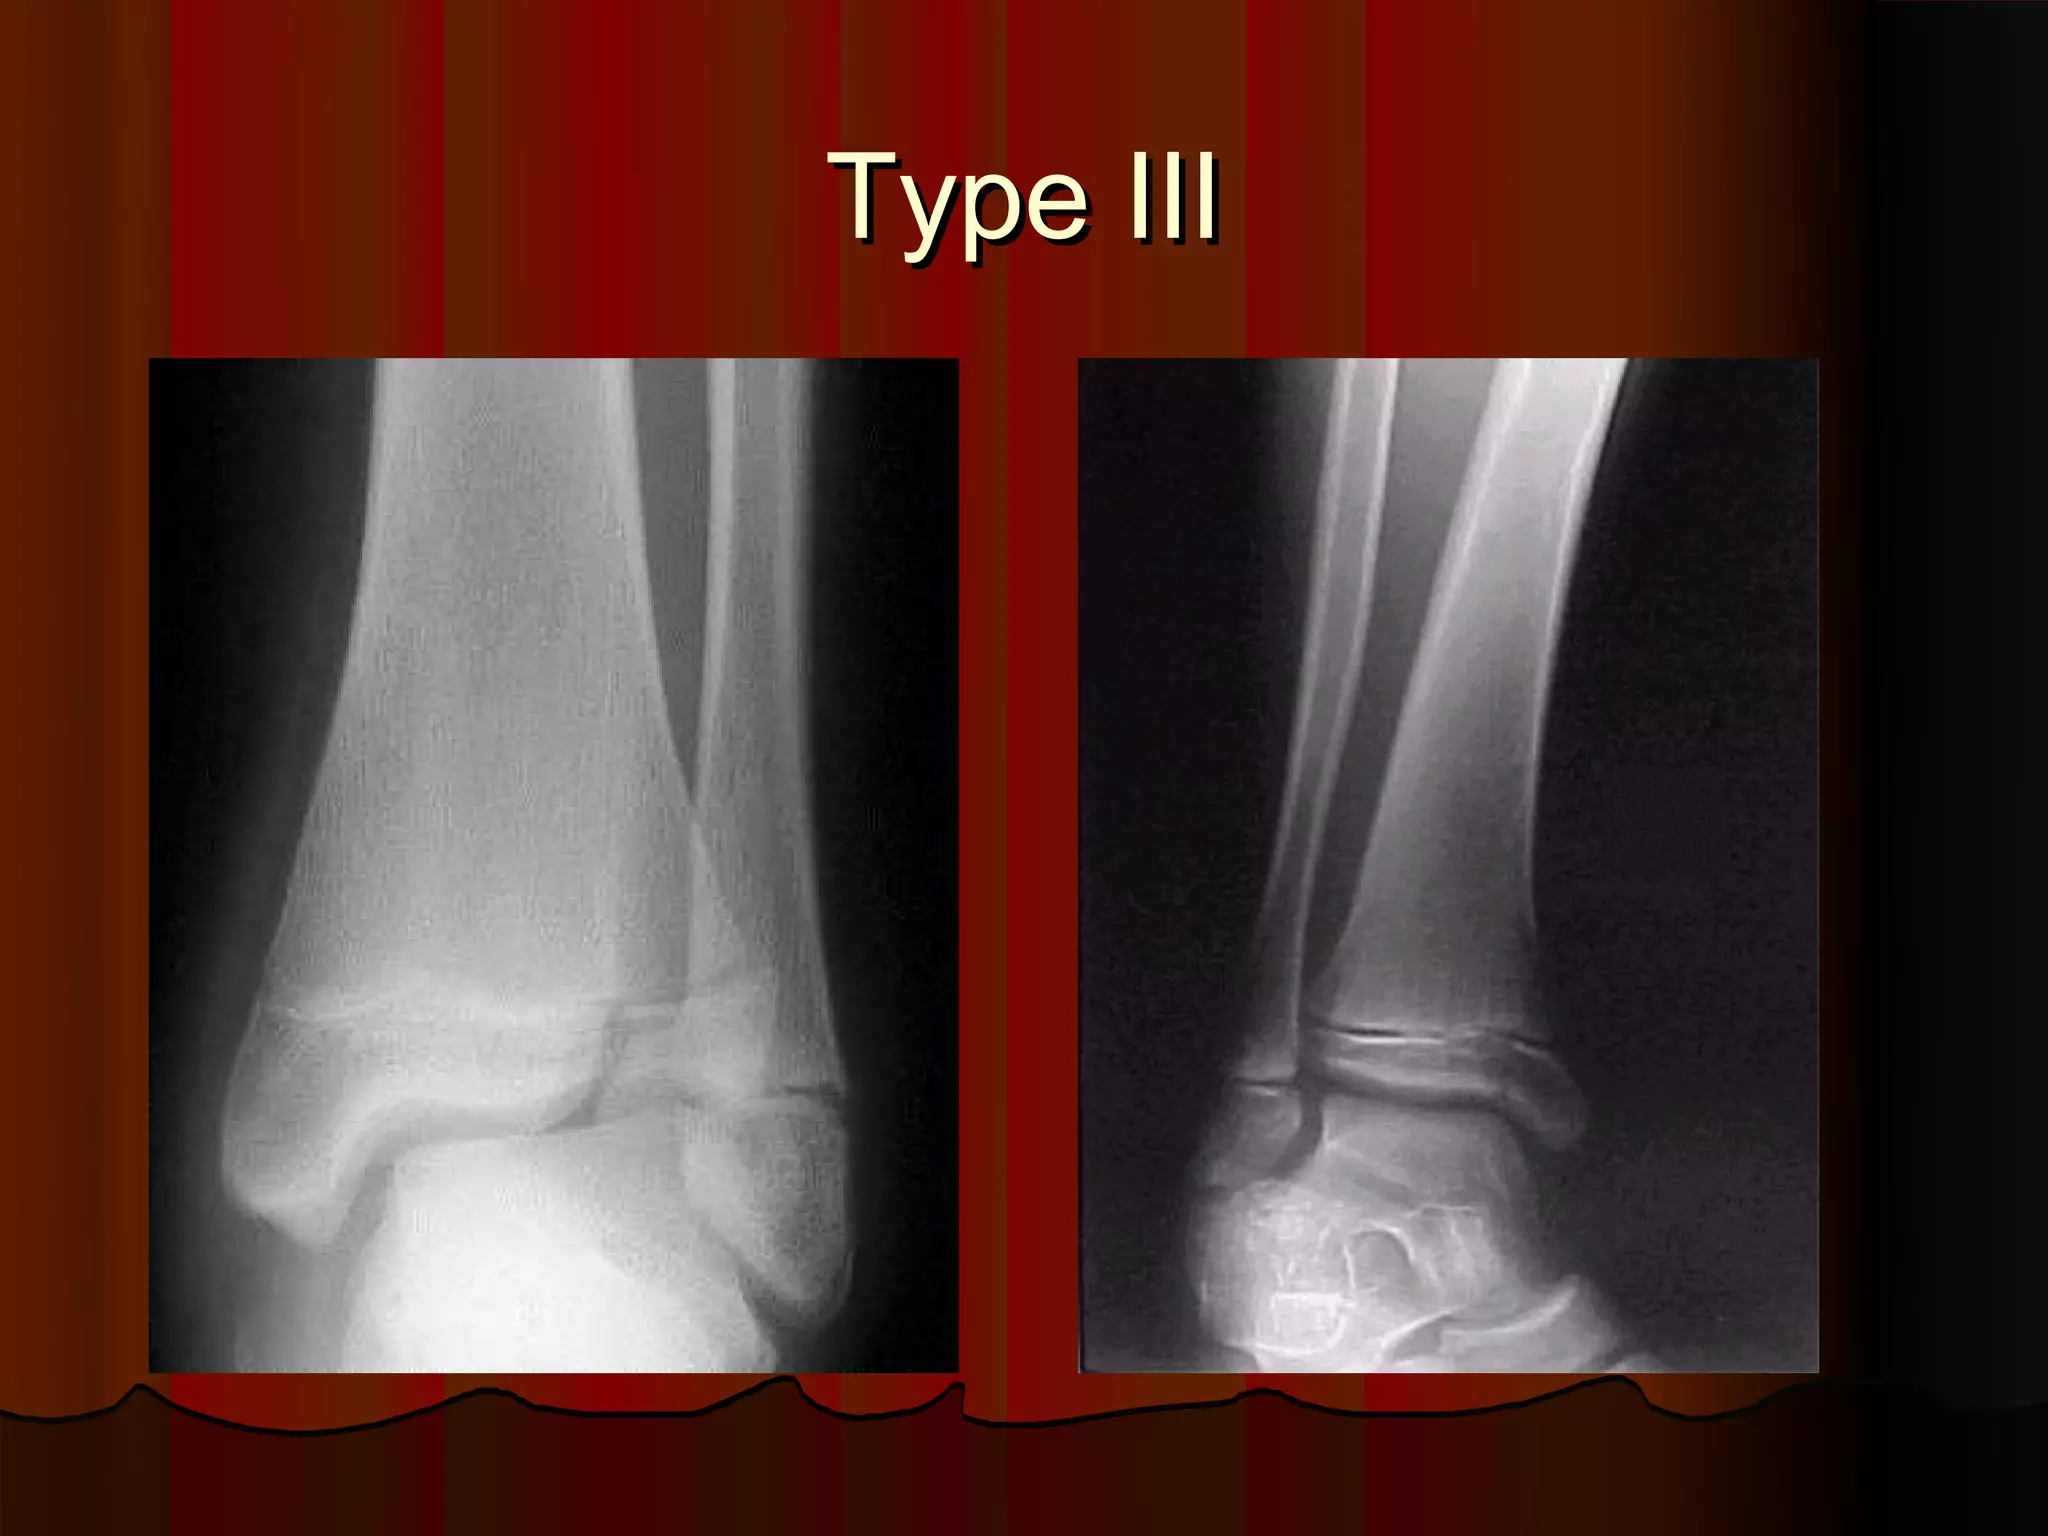

Description of Salter-Harris Type III injury.